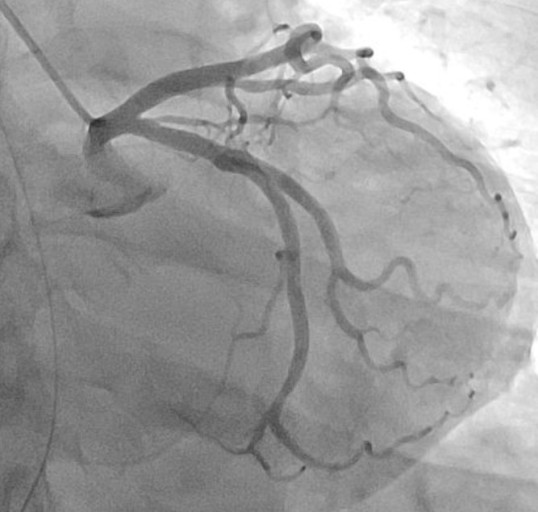

관상동맥 조영술: 심장 건강을 위한 필수적인 검사

관상동맥 조영술은 심장 근육에 혈액을 공급하는 관상동맥의 상태를 진단하는 검사입니다. 흉통, 호흡곤란 등 협심증이나 심근경색증 등의 증상이 있는 환자에게 시행합니다. 1. 검사방법 - 국소 마취 또는 진정제를 사용하여 시술 부위를 마취합니다. - 팔이나 다리의 동맥에 작은 절개를 하고 도관을 삽입합니다. - 도관을 통해 조영제를 주입하고 관상동맥을 촬영합니다. - 촬영 후 도관을 제거하고 절개 부위를 봉합합니다. 2. 검사주기 관상동맥 조영술의 검사 주기는 환자의 증상, 심장 건강 상태, 의사의 판단에 따라 달라집니다. 일반적으로 증상이 나타나거나 심장 건강 상태가 변화할 때 시행하게 됩니다. 3. 소요시간 관상동맥 조영술의 소요시간은 약 30분에서 1시간 정도 소요됩니다. 4. 주의사항 - 검사 전에 ..